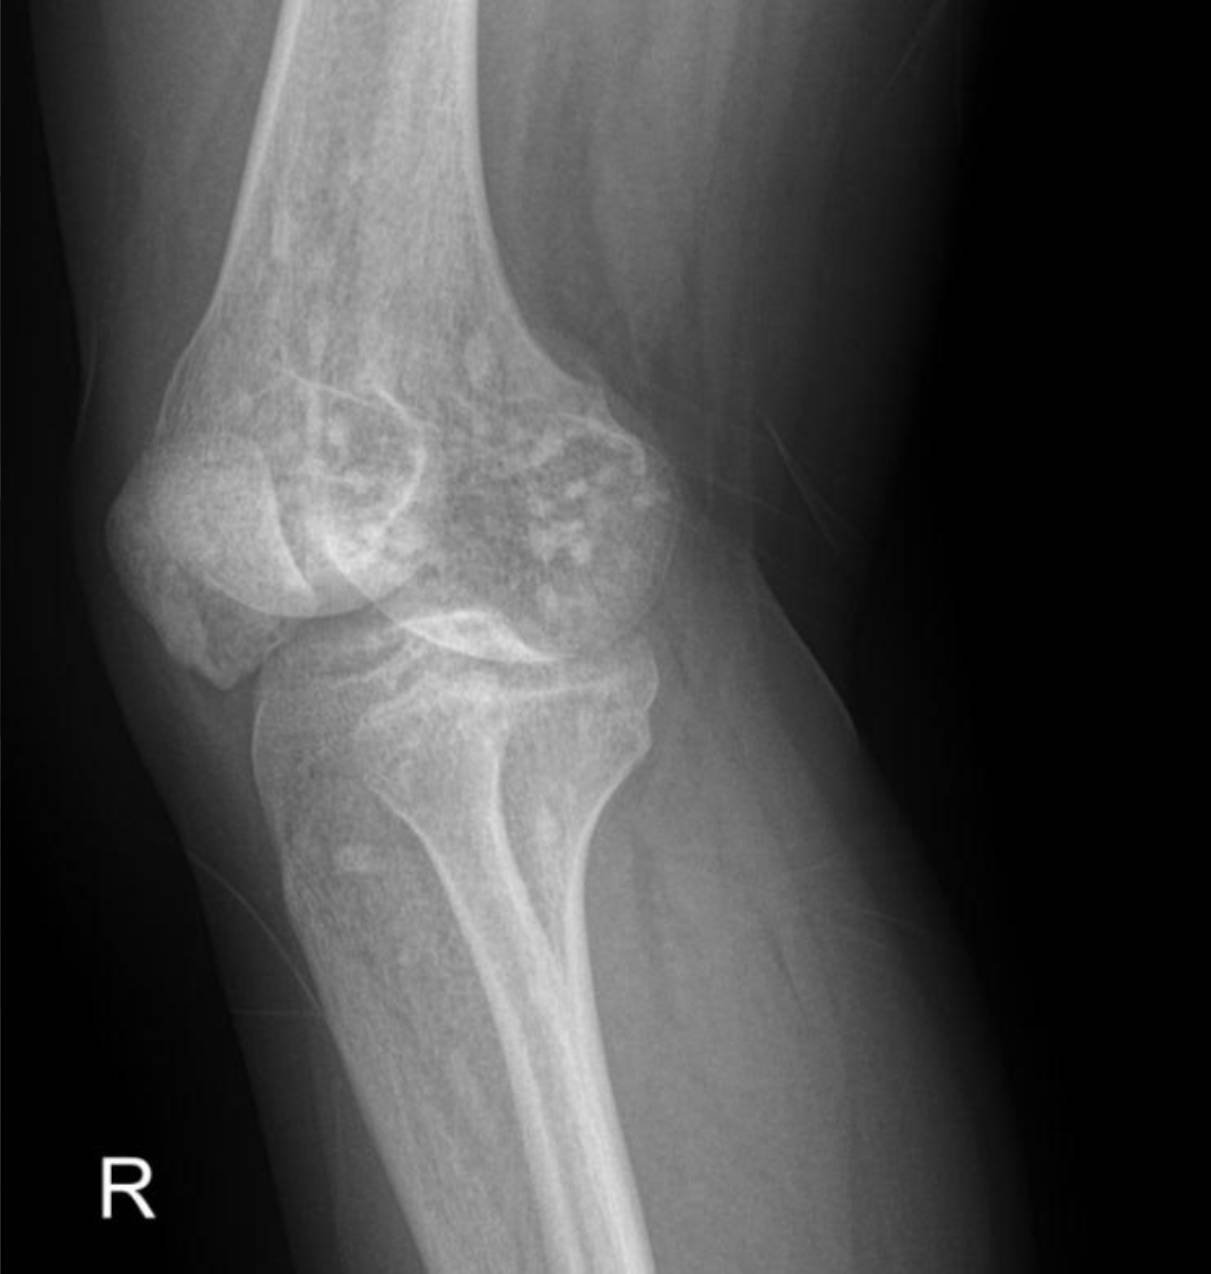

Radiological Findings: Skeletal X-rays (Incidental Discovery)

During the extensive workup for her hypertension and renal issues, skeletal X-rays were performed, which revealed a striking and unexpected finding.

The X-rays of the pelvis, knees, elbows, wrists, and ankles demonstrate multiple, discrete, well-circumscribed sclerotic (densely opaque) lesions distributed symmetrically throughout the bones. These lesions are typically ovoid or spherical, varying in size, and are predominantly located in the epiphyses and metaphyses of long bones, as well as in the carpal and tarsal bones and the pelvic girdle.

Specifically:

- Elbows: Similar sclerotic lesions are evident in the distal humerus and proximal ulna and radius around both elbow joints.

These widespread, symmetrically distributed sclerotic bone islands are pathognomonic for hereditary osteopoikilosis (also known as osteopathia condensans disseminata). This condition is typically benign and often discovered incidentally. While not directly related to her renal artery stenosis or hypertension, its discovery is crucial for patient management as it can sometimes be associated with other connective tissue disorders, though often it is an isolated finding.